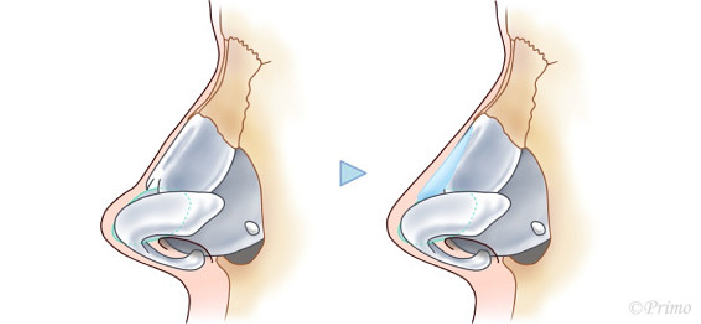

求める変化の大きさ、もともとの鼻の状態に応じ、採取部位を耳介軟骨、肋軟骨、あるいは鼻中隔軟骨から選択し、必要量のみ採取いたします。(上の図は耳介軟骨を採取して鼻中隔延長をするイメージ)

青い部分が移植した軟骨です。この軟骨の固定により、鼻の高さ、細さ、向きが大きく調節できます。